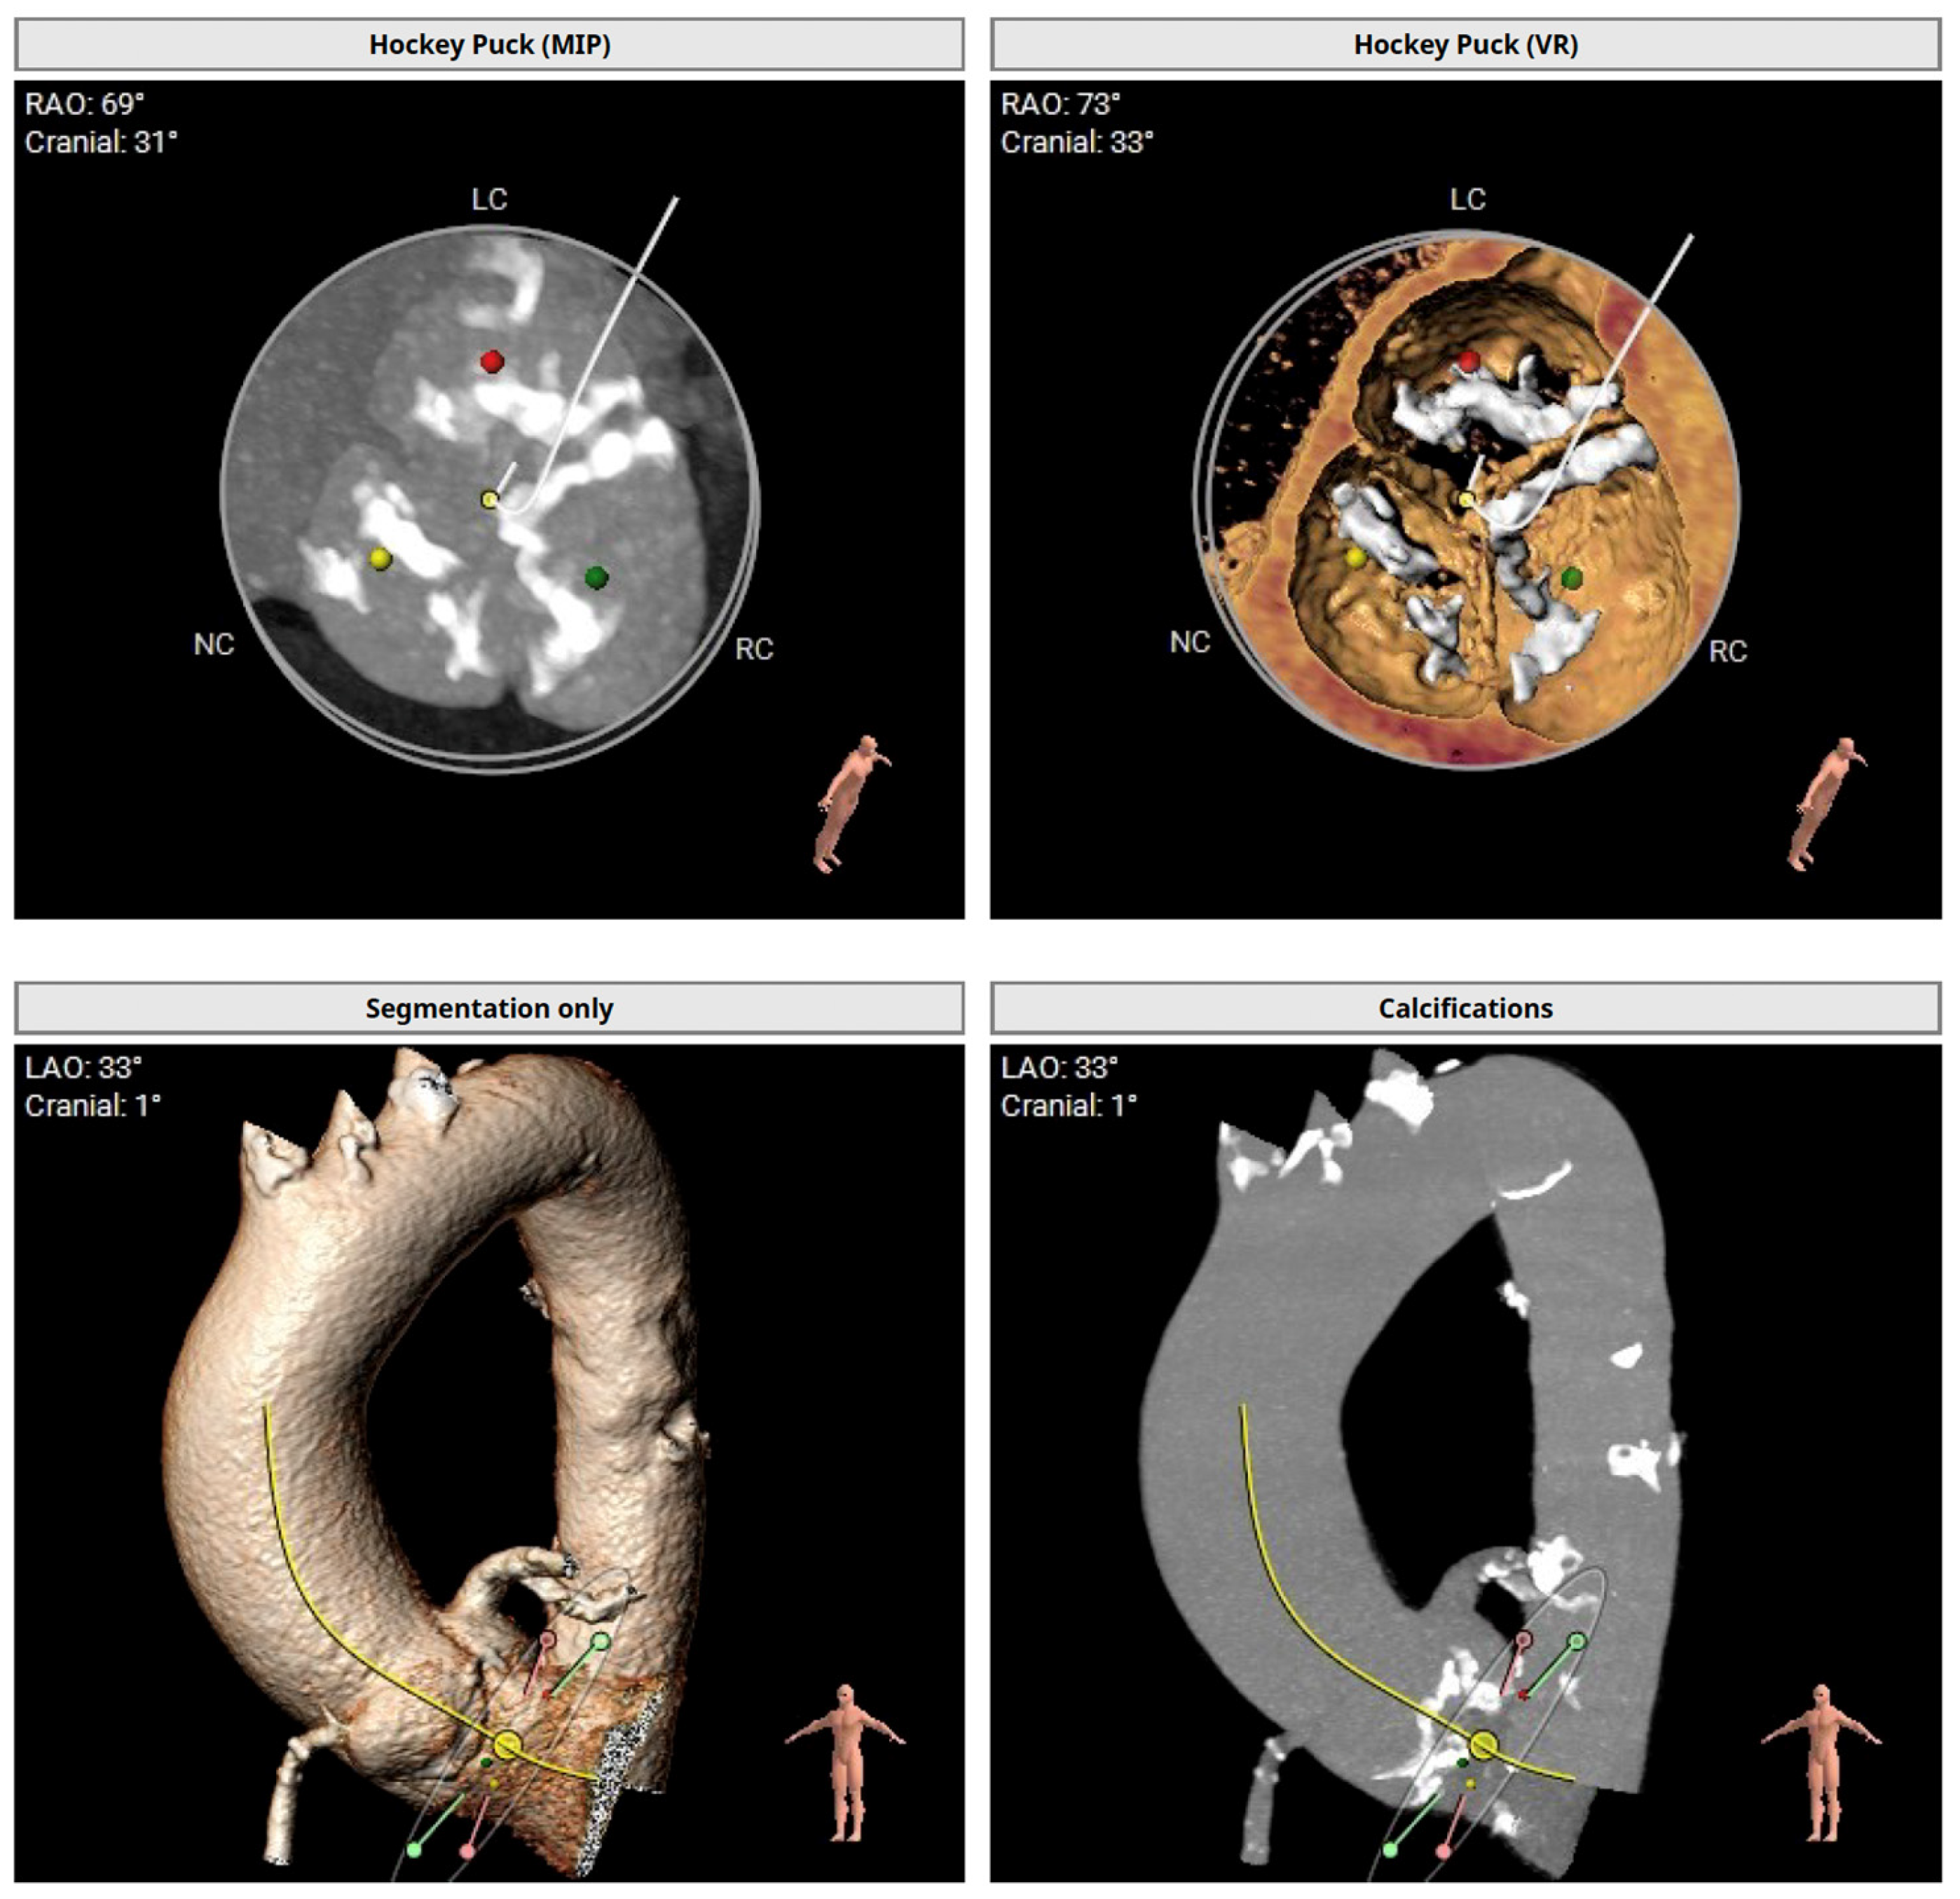

After recovery from the TAVI in the presence of clinical signs of heart failure, a chest X-ray and a repeat transthoracic echocardiography were performed to assess the position of the grafts (Figure 2).

Figure 2. Double transcatheter aortic valve implantation. The embolized prosthesis is in the ascending aorta (dashed arrow), and the second aortic valve prosthesis is in the correct position (arrow).